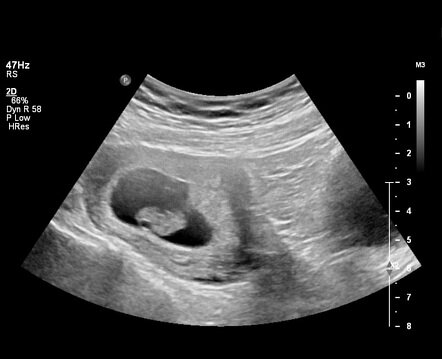

• 1st Trimester

1st Trimester

Months 1 through 3. Implantation occurs about one week after conception when the zygote nestles into the endometrium. This trimester is where the embryo develops most of the necessary vital organs. By the end of month 3, the fetus measures to be about 3 inches in length and weighs roughly 1/2 an ounce. From this point on, no new organs will be formed, the current organs will need to develop more.